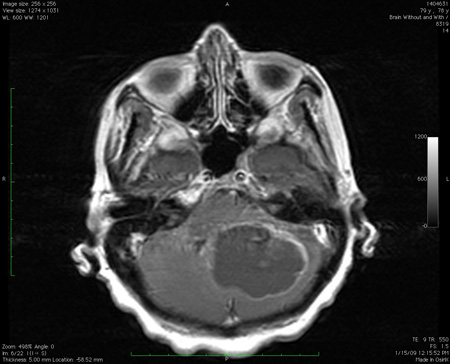

Lesão de massa grande no cerebelo com efeitos de pressão, conforme observado na ressonância nuclear magnética (RNM)

Do acervo de Dr. S. H. Subramony; usado com permissão